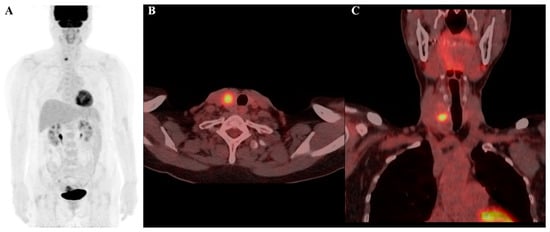

Figure 4.

F-18 FDG PET/CT image of a 69-year-old female patient, highlighting a thyroid incidentaloma in the right lobe of the thyroid gland: (A) maximum intensity projection (MIP); (B) axial PET/CT image; and (C) coronal PET/CT image. The lesion demonstrates increased FDG uptake with a maximum standardized uptake value (SUVmax) of 9.2. Radiomic features include a log-sigma-2-0-mm-3D_glszm_SmallAreaEmphasis value of 0.553 (relatively low) and a wavelet-HLH_gldm_LargeDependenceLowGrayLevelEmphasis value of 33.814 (relatively high). Despite the high SUVmax, the final diagnosis confirmed the nodule to be benign.